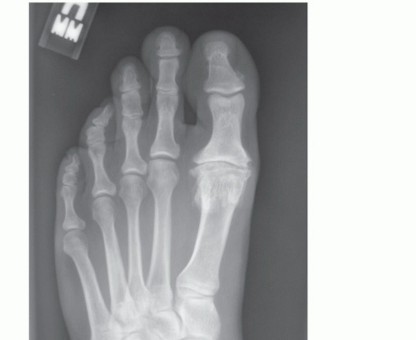

Grade III: marked osteophyte formation with loss of joint space and subchondral cyst formation (FIG 1).

FIG 1 • A. AP view of a foot with hallux rigidus with a relatively longer second metatarsal and the suggestion of second metatarsal overload with flattening of the metatarsal head. B. Lateral view of the foot demonstrating dorsal osteophytes and joint space narrowing.

Long second metatarsal (potential risk for development of transfer metatarsalgia) (see FIG 1A) Hallux valgus